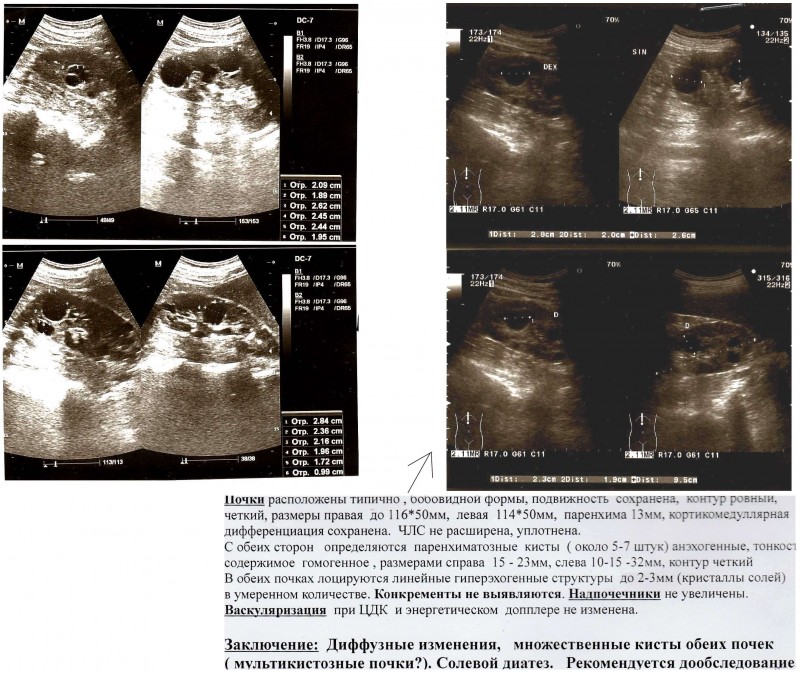

температура нормализовалась, белки глаз побелели, дальше колоть не стал выпил (глюкозу) так. Сделал узи почек в двух разных клиниках, получил поликистоз и мультикистоз. Результат анализа на гепатиты отрицательный nav ig g+. Рекомендация инфекциониста обследование на синдром жильбера. Гастроэнтеролог заключение: диффузный поверхностный гастрит. Поверхностный бульбит желчь в желудке.

назначения диета, хофитол, дюспаталин. Уролог заключение: Необструктивный хронический пиелонефрит, связанный с рефлюксом n11.0, n28.1 Кардиолог заключение: пролапс митрального клапана 1ст всд по смешанному типу множественные кисты обеих

почек, марфаноподобный синдром, рекомендации ттг, т4, а/т к тпо при необходимости консультация